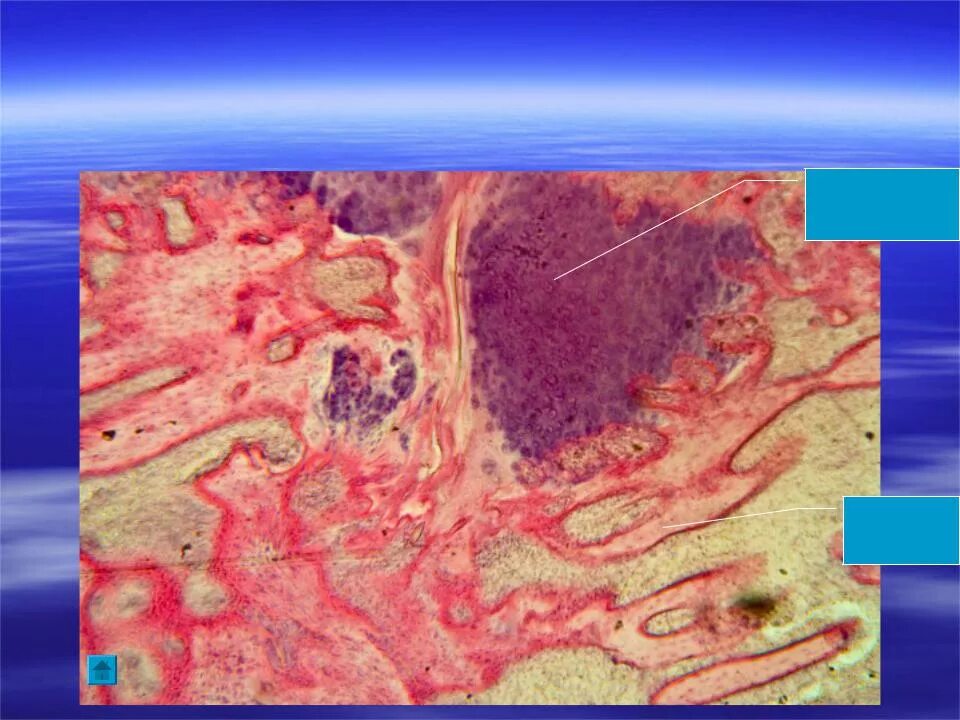

Стадия тканей